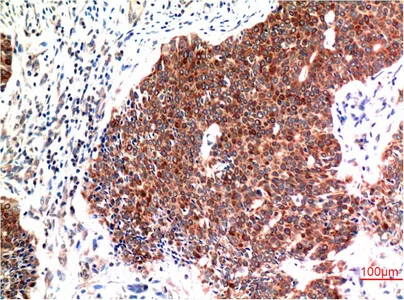

Galectin-3(8D7)Mouse Monoclonal Antibody

ERK1/2(1H4)Mouse Monoclonal Antibody

Beclin-1(5C2)Mouse Monoclonal Antibody